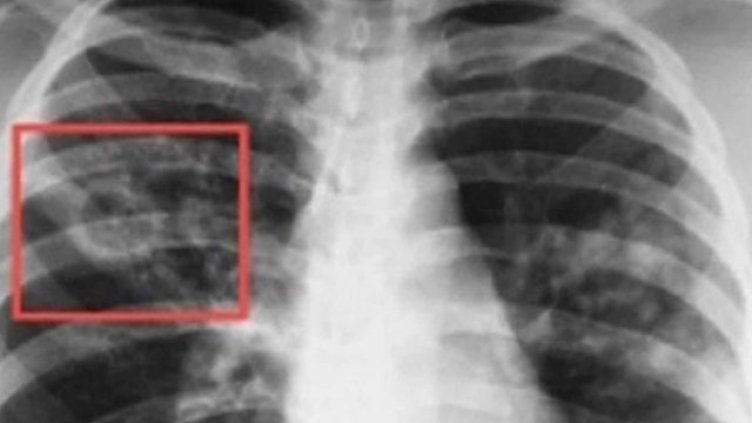

По време на „Седмицата на отворените врати“ на всеки желаещ се предлага скрининг за риска от туберкулоза чрез анкета и консултации. На лицата, които са в риск, се провеждат допълнителни прегледи и изследвания. При откриването на случаи на туберкулоза своевременно се предприемат мерки за хоспитализация и лечение, в резултат на което се прекъсва веригата за предаване на инфекцията.

По време на проведените за периода 2009 г. – 2022 г. „Седмици на отворени врати” са анкетирани за туберкулоза над 125 000 лица, открити и насочени за лечение са 1 376 лица с туберкулоза, открити с латентна туберкулозна инфекция и обхванати с химиопрофилактика са 4 655 души.

В резултат на изпълнението на Националните програми за превенция и контрол на туберкулоза в България e налице тенденция за трайно намаляване на заболяемостта от туберкулоза - от 26.6 на 100 хил. население през 2012 г. до 14.8 на 100 хил. през 2022 г. (по предварителни данни).